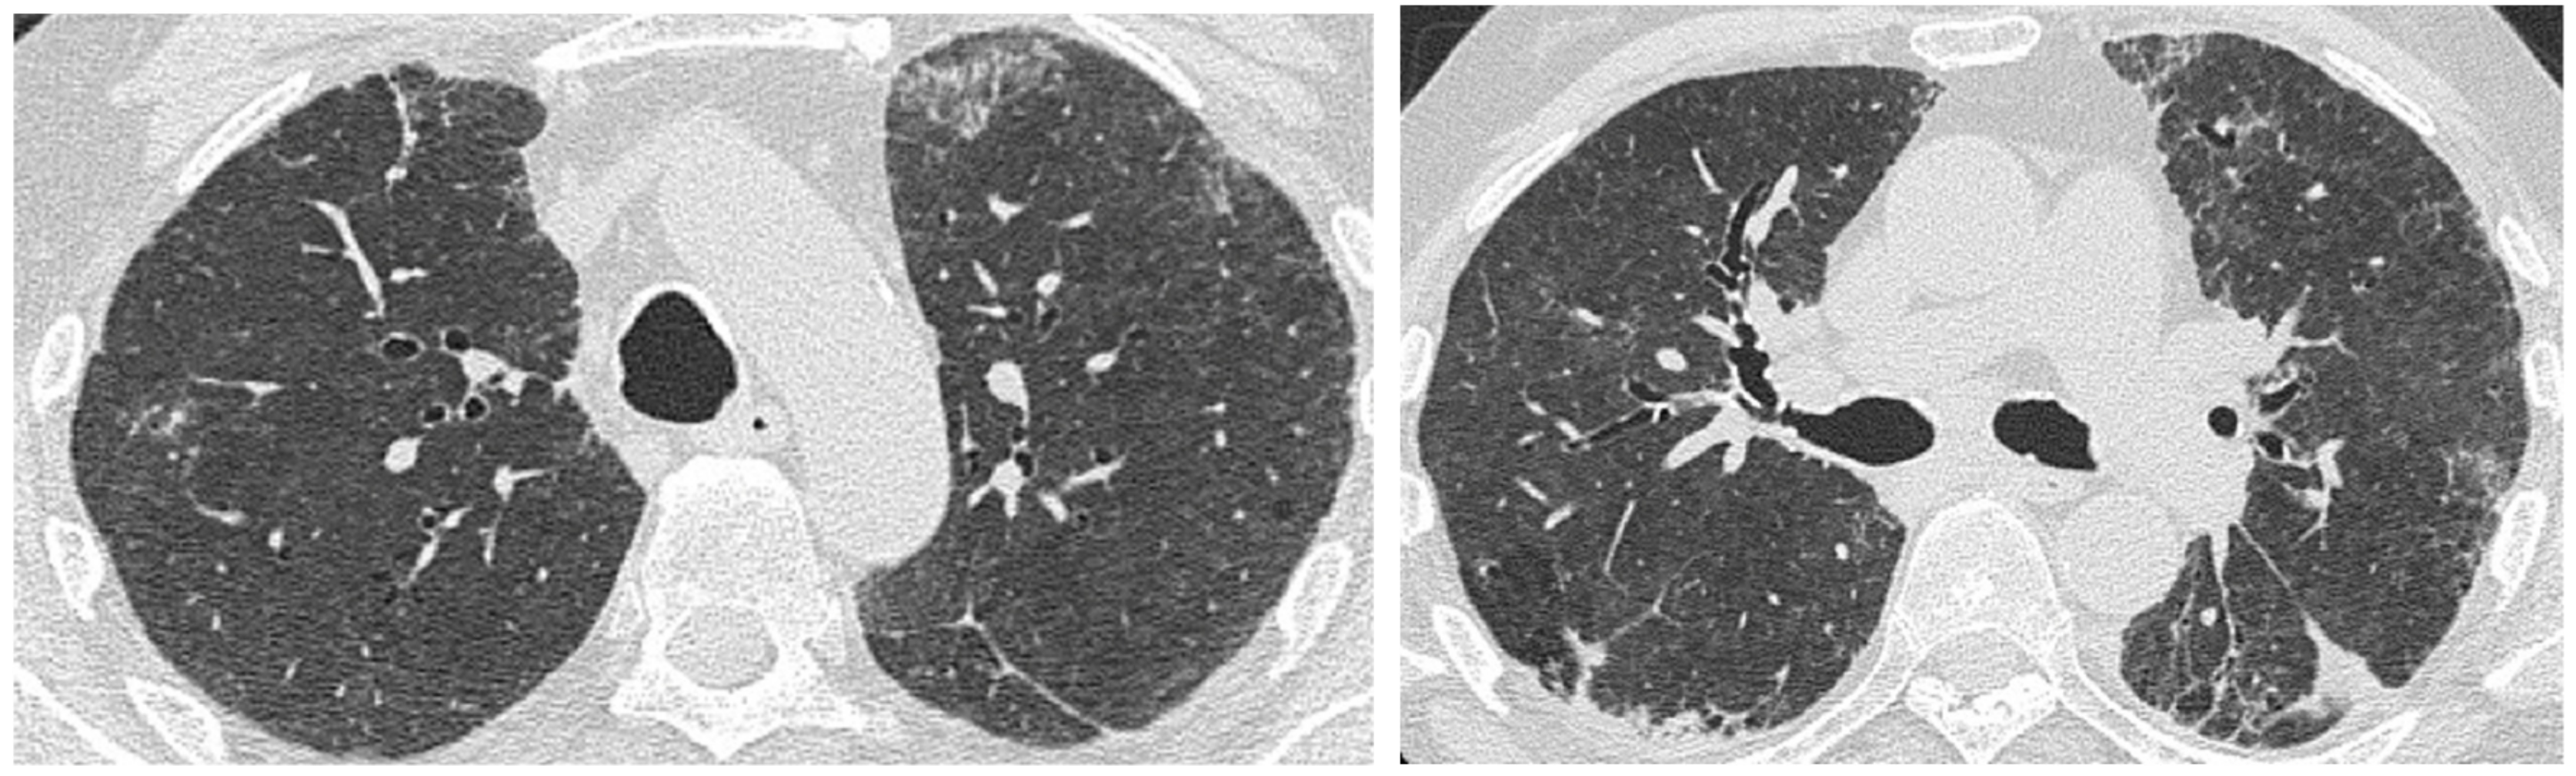

| Acute | Infections | Mycobacterium species | Peripheral mass-like lesion/subpleural nodules/segmental or lobar coalescent consolidation with or without necrotising cavitation. |

| Pneumocystis jirovecii | Ground glass opacity/no change from the baseline in a clinic context of infection. | ||

| Aspergillus | Fungal fronds in a pre-existing cavity in early stages. Subsequent coalescence of the cavity (air crescent sign). | ||